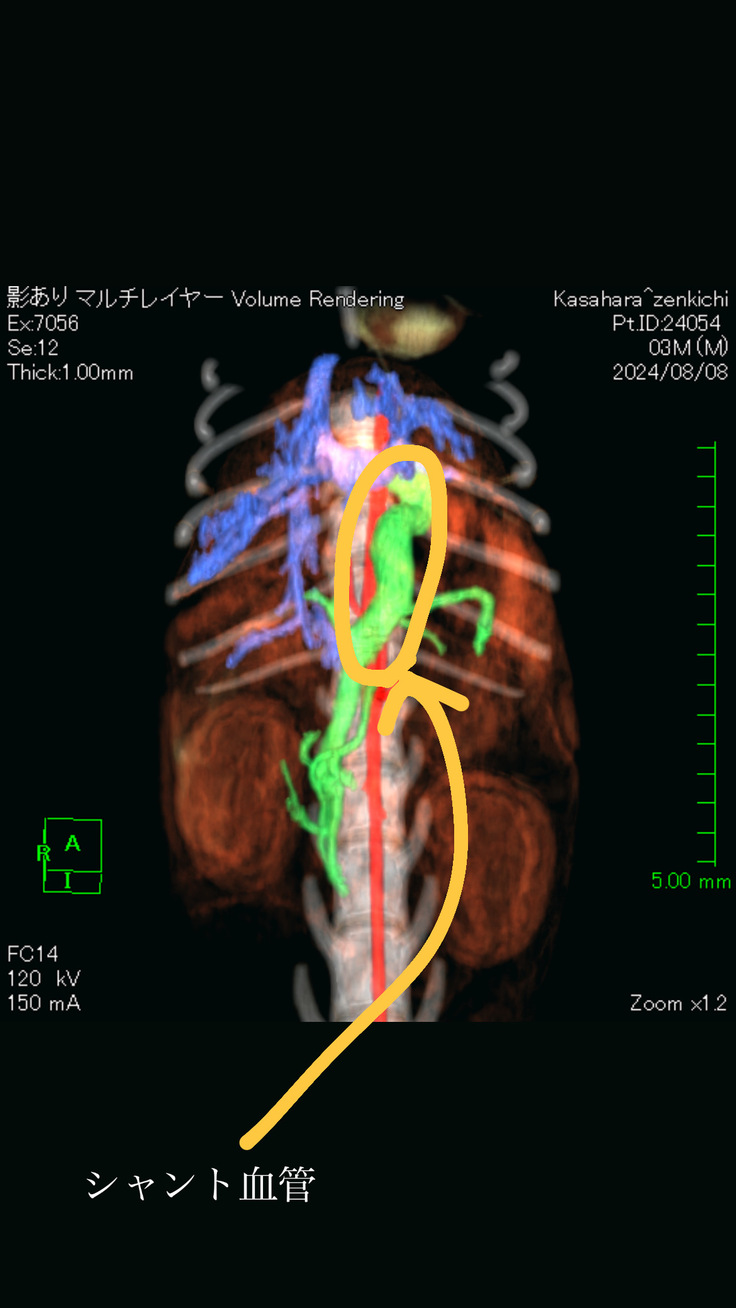

8/8、同じくB病院にてCT検査

CT検査

CT検査の結果【門脈体循環シャント】と診断されました。

門脈体循環シャントとは・・・

本来、肝臓で解毒されるはずのアンモニア等の毒素が門脈と全身の静脈を繋ぐ余分な血管(シャント血管)によって全身を巡ってしまう疾患です。

食事で摂取したたんぱく質が体内で代謝されると同時に、アンモニアや短鎖脂肪酸等の毒素が作りだされます。本来、これらの毒素は腸管から吸収され、門脈を通って肝臓でに運ばれ、肝臓内で無毒化されます。

門脈シャントとは何らかの原因で門脈が枝分かれしてしまっている場合、毒素をもった血液が、本来通るべき肝臓を通らずに体循環と合流してしまう事で、毒素が全身を巡り様々な症状を引き起こします。

またシャント血管も太いため(上記CT画像参照)、十獣医師によると、結紮手術はできないが、リングをはめて徐々に血管をしめていく手術(アメロイドストリクター設置)になるとのことでした。